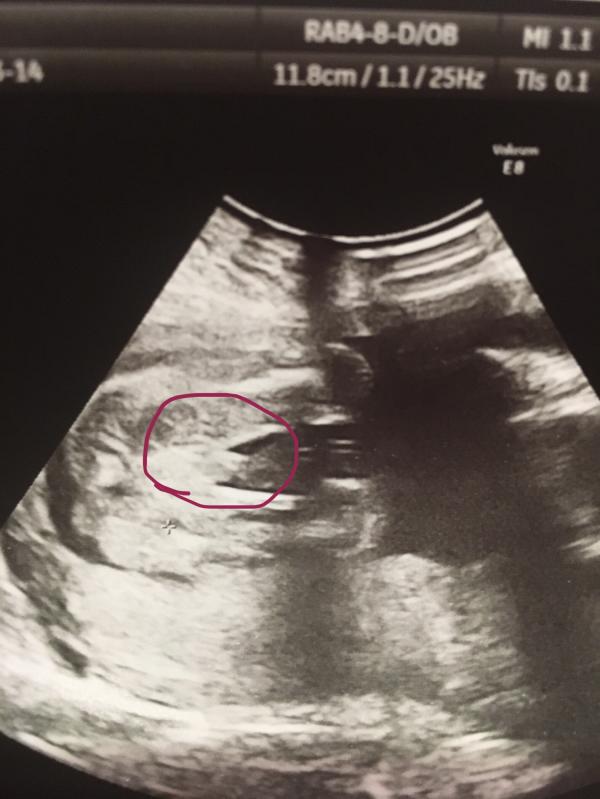

Просто врач говорит прячется, плохо видно, я то пипку вижу, но что немного выше?! Главное, чтобы здоровенькие) Окружающие с толку сбивают, живот на девочку, нос на девочку😂 Муж, мама говорит, что девочка. Вот и я начинаю это УЗИ разглядывать😅

@tender_kiss15, ааа) а узист мальчика сказал ?) на мальчика больше подходит

@vash.conditer, да, сказали мальчик, но муж говорит, что не видит пацана и все вокруг говорят, что девочка у меня🤪 никак не могу настроиться...

@tender_kiss15, если долго вниз мои записи полистать там тоже такая пипка) так что настраивайтесь , мальчик 😁